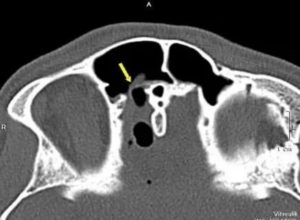

- Компьютерная томография (КТ) основания черепа и околоносовых пазух (на рисунке определяется большой дефект основания черепа в проекции ситовидной пластинки с формированием менингоцеле (показано стрелкой)).

- КТ-цистернография с эндолюмбальным введением контраста для более точного определения расположения дефекта в основании черепа. Это исследование выполняется в условиях стационара.